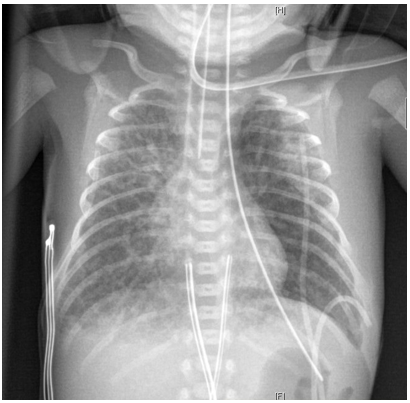

Pulmonary Hydatid Cyst with Broncho-Pleural Rupture: A Rare Complication to be Considered (Case Report)

Ali Haidar, Ahmed El Mostarchid, Lina Blekouchi, Nazik Allali, Siham El Haddad and Latifa Chat. 13(8): 01-04.